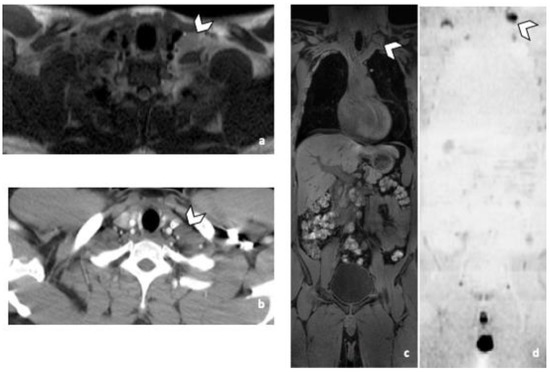

Figure 5.

45-year-old man with seminoma. Axial CT image (a) and T2-weighted (b), 3D T1 GRE Fat-Sat (c) and high b-value DWI (b = 1000 s/mm2) (d) MR images. Left pulmonary nodule (arrowhead) detected by both readers during CT and MRI readings. Abbreviations: 3D: Three Dimensional, T1 GRE: T1 Gradient Echo, DWI: Diffusion Weighted Imaging, MRI: Magnetic Resonance Imaging, CT: Computed Tomography.